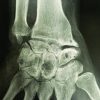

A 16-year-old female presented with the left thigh swelling and pain for 3 months. There was a palpable mass deep to the quadriceps muscle on the medial side of the thigh, but no evidence of metastasis. Complete blood cell count, erythrocyte sedimentation rate, C-reactive protein, and renal function tests were normal. X-ray of the left femur showed an osteosclerotic tumor in the medial aspect of the middle third of the left femur (Fig. 1). Open biopsy was done and histomorphologic evaluation of the sample revealed a tumor composed of pleomorphic spindle cells having a dense eosinophilic cytoplasm, marked nuclear atypia, and brisk mitotic activity. Areas of necrosis, deposition of thin, lace-like malignant osteoid, and chondroblastic differentiation were noted, features consistent with osteogenic sarcoma (Fig. 2).